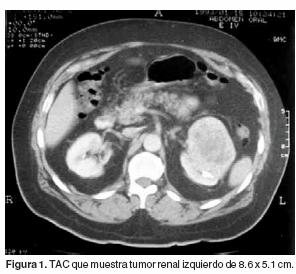

Carcinoma de Células Renales: Estadificación Prequirúrgica ...

Suntivo de carcinoma renal. Criterios de inclusión: pacientes de ambos sexos con tipos de tumores renales: carcinoma de células claras (Fig. 1) en 37 casos, de tipo papilar (Fig. 2) en 2 casos y cromófobo (Fig. 3) en un solo caso. ... Retrieve Document